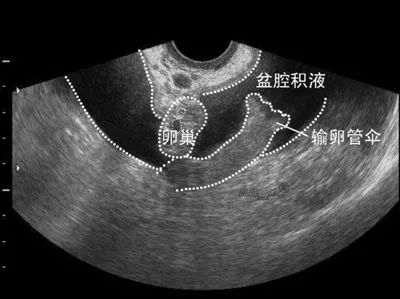

举例来说,某些患者问“我有盆腔积液,那我是有炎症吗”,仅依靠超声检查是很难得出结论的。

盆腔积液可分为生理性盆腔积液和病理性盆腔积液。生理性盆腔积液是因为盆腔是腹腔在全身最低的部位,当有渗出液或漏出液时都会引流到盆腔,从而形成盆腔积液。部分正常妇女在月经期或排卵期会出现彩超结果中的盆腔积液,但没有任何症状。此时无需治疗,定期观察即可。而有病理性盆腔积液者要及时到医院就诊,对症治疗。

B超可以观察到盆腔积液的存在,但是无法彻底分辨其性质,还需要依靠抽血化验,观察血象变化,以及妇科检查共同诊断。